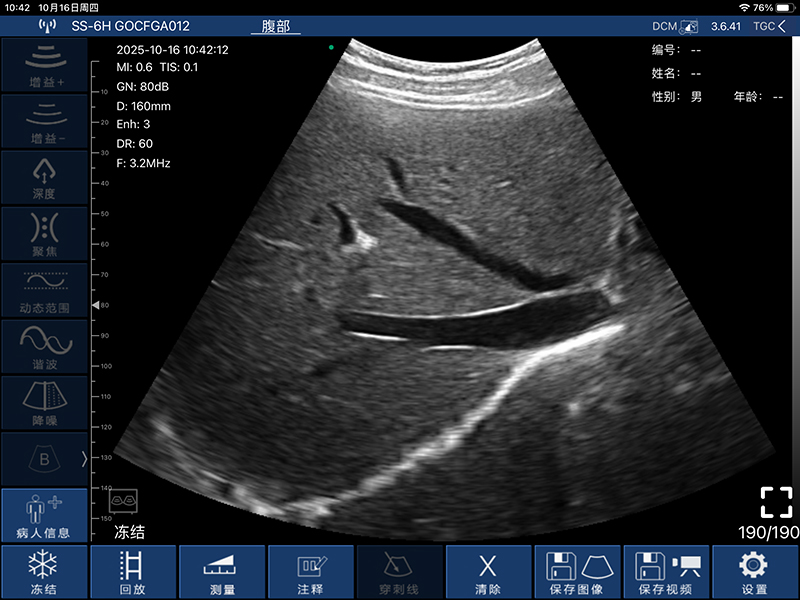

• 扫描方式:电子阵列扫描

• 探头频率:3.2/5.0MHz

• 扫描深度:90/160/220/305mm,可调

• 显示模式:B、B/M、Color、PW、PDI